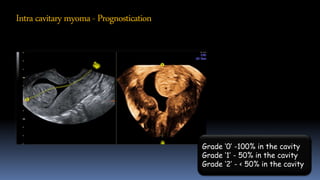

Intracavitarymyoma- Prognostication

Grade ‘0’ -100% in the cavity

Grade ‘1’ - 50% in the cavity

Grade ‘2’ - < 50% in the cavity

Intracavitarymyoma- Prognostication Grade ‘0’-100% in the cavity Grade ‘1’ - 50% in the cavity Grade ‘2’ - < 50% in the cavity